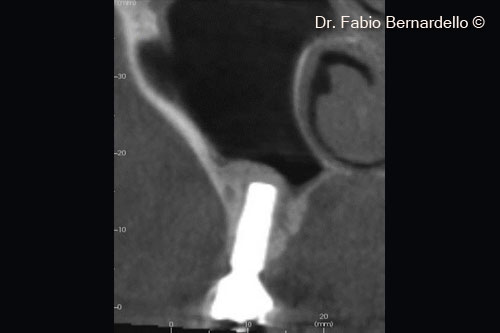

Hình ảnh X-Quang 7 tháng 6 phẫu thuật cho thấy Gel 40 đã được tái tạo thành xương mới phía trên vùng cấy ghép mới

Hình ảnh X-Quang 7 tháng 6 phẫu thuật cho thấy Gel 40 đã được tái tạo thành xương mới phía trên vùng cấy ghép được đặt 10 năm trước